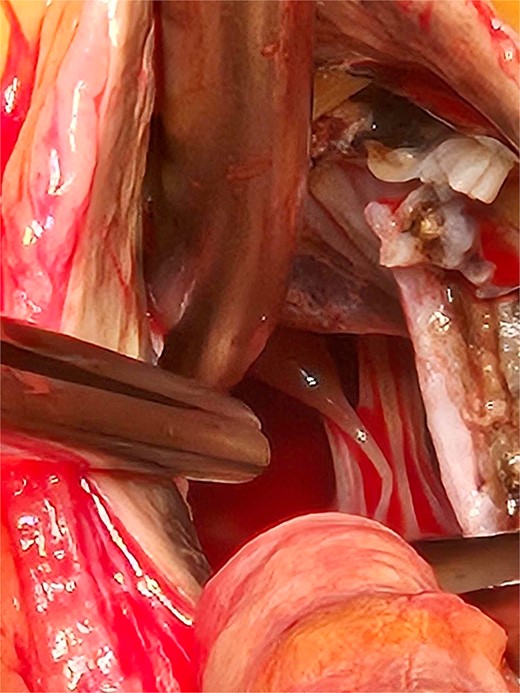

Based on these findings, the patient underwent surgical aortic biological valve replacement and coronary artery bypass grafting (CABG) using a left internal mammary artery graft to the LAD. Intraoperatively, unexpected ochronotic pigmentation was observed in the aortic and mitral valve leaflets, papillary muscles, and the intimal layer of the aortic root, presenting as patchy black discoloration (Figs 1–3). Subsequent biochemical analysis confirmed elevated homogentisic acid levels in the urine, consistent with alkaptonuria.

The patchy ochronotic discolouration can be visualized along the aortic root walls and extending below towards the mitral valve.

The patchy ochronotic discolouration can be visualized along the aortic root walls, and along the aortic valve leaflets, being more prominent along areas of heavy calcification.

The extent of the ochronotic uptake can be seen extending to the level of the papillary muscles.